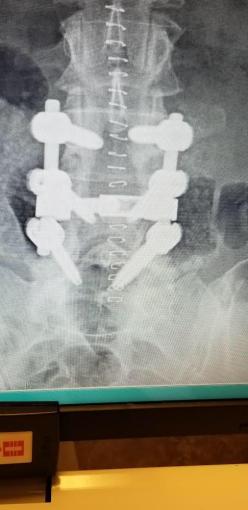

While recuperating from my most recent spine surgery, I planned a 1920s/Gatsby-style ladies luncheon to celebrate my Mom’s 89th birthday. (Doesn’t she look beautiful??? Don’t tell me this chick “Ain’t Misbehavin'”!!!) A grand luncheon in her honor has become sort of a tradition (when I’m healthy!) since her 2011 retirement from the Missouri Senate, and it’s always a delightful challenge to come up with a theme that both she and her guests will enjoy. (Check out 88 Years & 88 Keys, Celebrating 85 Years of Fabulous, Pretty In Pink, Grazin’ in the Grass.) This year’s inspiration came from a flapper bar towel my friend/neighbor, Barbara, gifted me while I was convalescing. Mom was born in the March preceding the start of the Great Depression in 1929, and I thought it would be a fun idea to travel back in time to explore the good things about that (infamous) year!

While recuperating from my most recent spine surgery, I planned a 1920s/Gatsby-style ladies luncheon to celebrate my Mom’s 89th birthday. (Doesn’t she look beautiful??? Don’t tell me this chick “Ain’t Misbehavin'”!!!) A grand luncheon in her honor has become sort of a tradition (when I’m healthy!) since her 2011 retirement from the Missouri Senate, and it’s always a delightful challenge to come up with a theme that both she and her guests will enjoy. (Check out 88 Years & 88 Keys, Celebrating 85 Years of Fabulous, Pretty In Pink, Grazin’ in the Grass.) This year’s inspiration came from a flapper bar towel my friend/neighbor, Barbara, gifted me while I was convalescing. Mom was born in the March preceding the start of the Great Depression in 1929, and I thought it would be a fun idea to travel back in time to explore the good things about that (infamous) year!